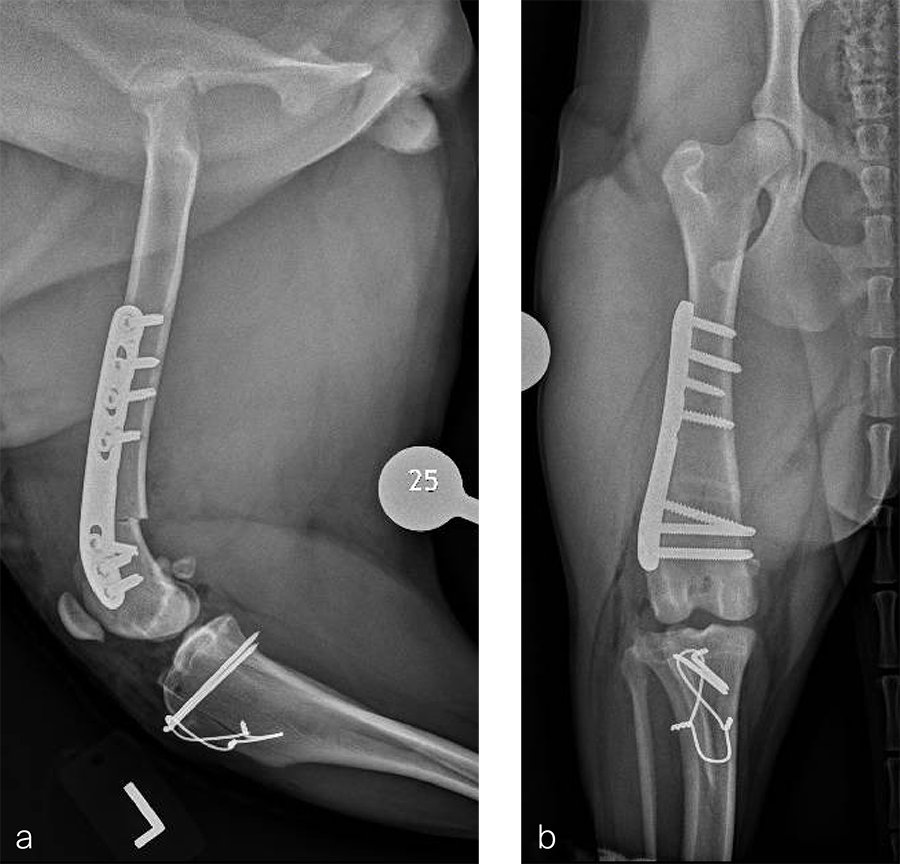

Fig 5a–b Postoperative radiographs demonstrating position of a left, 7-hole, 3.5 LCP DFO plate and associated tibial tuberosity transposition. a Medioateral view. Note that plate contour matches the normal distal femoral procurvatum and screws are positioned caudally away from the trochlea. This allows for an unimpeded sulcoplasty while maximizing screw purchase caudally. The compression applied with the plate has resulted in excellent apposition. The patella is visible within the trochlear groove. b Craniocaudal view. The plate contour matches the anatomical contour of the distal femoral condyle. The anatomical Lateral Distal Femoral Angle is reduced to 92°.

Fig 6a–b Follow up after eight weeks. Clinical signs have resolved, limb use is excellent, and stifle joint range of motion is normal without evidence of pain. a Mediolateral radiograph. The osteotomy has healed. Plate and screw position remain unchanged. The tibial tuberosity transposition is healing, and implants remain unchanged. The patella remains reduced within the trochlear groove. b Craniocaudal view. The osteotomy has healed and is no longer visible. Implants are stable and the patella is tracking normally.